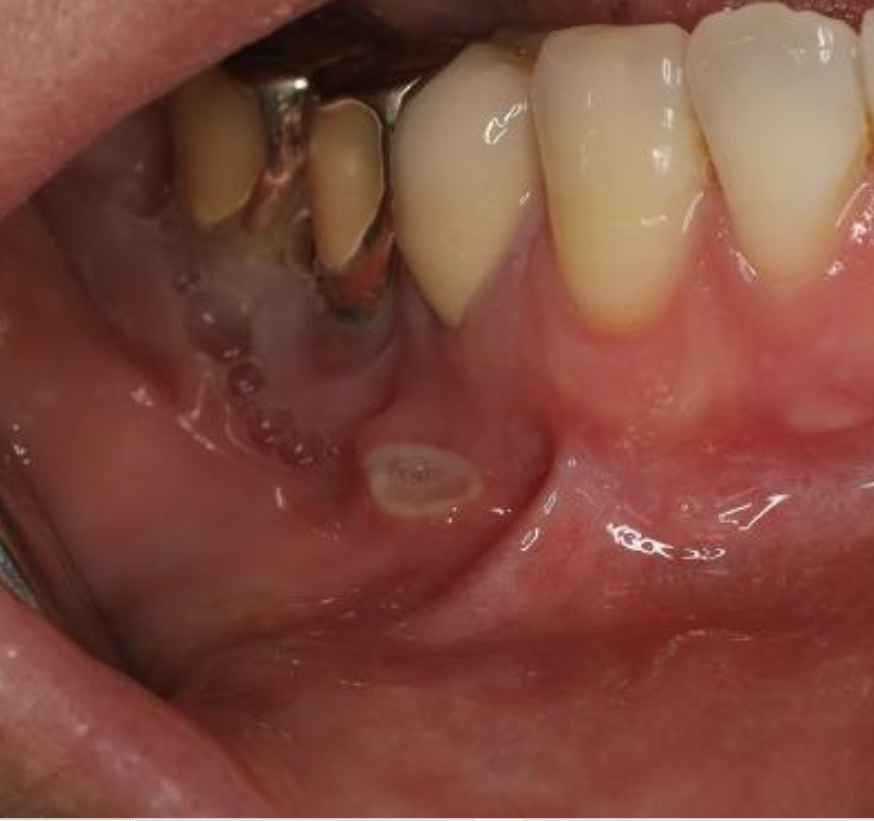

(실제 나의 뺨 점막 사진입니다)2. 염증의 양상이 없어지지 않고 뺨 점막 붉은 병변 및 아픈 통증 5. 교정 보철물 및 물고 온 상처가 시간이 지나도 없어지지 않을 경우 나는 2009년경에 치아 교정을 시작한 2011~2012년경 교정이 끝났어요 교정 치료를 하며 교정기 보철물로 뺨 점막이 더 많이 찔리고 긁히거나 하는 경우가 발생할 거요 정확하게 언제부터 적체증과 아픈 통증이 시작됐는지는 기억 나지 않지만 교정 치료가 끝난 후 시간이 지나고 식사를 하고 있고 오른쪽 뺨 점막 같은 곳을 강하게 몇번 씹은 기억은 있습니다. 붉은 병변과 아픈 통증을 내가 알고부터 5년 이내입니다 엄청 오래 된군요(?) 이렇게 하면 나도 구강 암 증상을 보면서 더욱 걱정이 되어 맞게 되었습니다 그래서 내가 2017년 동네 이비인후과 가장,2019년 동네 치과 방문 2020년 12월 직장 인근 여의도 치과 스케일링 겸 방문, 그리고 최근 2021년 2월 여의도 외의 치과 방문 등 4곳의 다른 병원에 가 봤어요 그 전에 붉은 병변과 아픈 통증은 계속되어 너무 걱정에서 최근 암 카페 현직 구강암 의사 분에 메모로 사진을 보내고 증세와 함께 들어 보았습니다 그 의사는 일반적인 염증의 양상과는 달리 보이기에 대학 병원의 조직 검사를 받도록 권하고 주신 당연히 그 의사는 직접 본 것이 없는 나의 증세와 사진상으로만 보던 거니까 정확한 진료를 받지 못하는 부분임을 참고하세요

아무튼 조직검사 얘기까지 들으니까 더 걱정이 몇 배나 돼서 다시 여의도에 유명한 치과를 예약하고 내원했는데 내원한 치과의사 원장님도 그 전에 내원했던 이비인후과 치과에서도 직접 만져보고 자세히 보시고 의사분들 비슷한 얘기를 해주셨어요 뭔가 세게 씹어서 생긴 상피표면의 상처 같다 그리고 치아교합이 문제되는 부분인 것 같다 결과는 시간이 오래됐지만 일단 씹어서 생긴 상처 같기 때문에 연고 및 치과처방 가글 항생제를 처방해서 치료해보시고 그래도 뭔가 문제가 된다면 그때 또 조직검사를 해보셔도 좋을 것 같아요.였습니다. 제가 교합 및 자세에 따라 무언가를 씹을 때 혀와 뺨의 교합 부분이 계속 볼 점막 쪽을 씹기도 한다고 합니다.